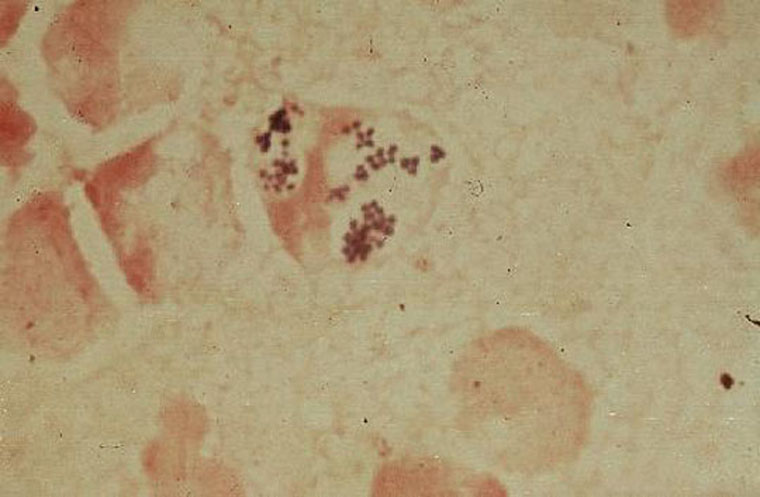

Staphylococcus Aureus: a gram stain of a smple of fluid from a skin lesion reveals clusters of gram positive cocci. Several neutrophiles are noted.  (Dr Ralph Leischner)

Pus smear (wound) Staphylococcus aureus  (Dr Tadayo Hashimoto)